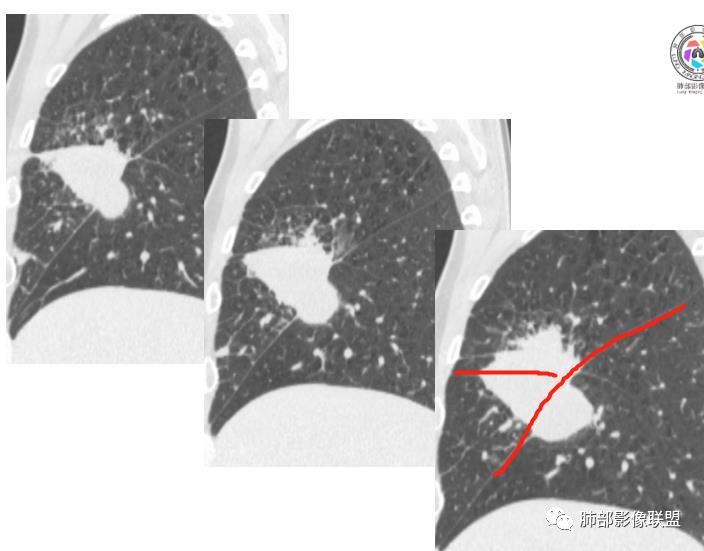

初学者:

可以看到斜裂一侧往上一侧往下,那么就是说病灶应该是起源中叶,往上,往下侵犯这样

是这样吗?

往下叶这个地方是突然就鼓出来了,这个地方还是应该叶裂缺限。

如是上叶的,叶间裂的方向应该是往一侧压得

只有这个位置起源得才能做到,将叶间裂上下往不同方向推

斜裂向下推移了,水平裂向上推移了。

下半段斜裂推移朝下

水平裂推移朝上

定在中叶应该没问题

深分叶

上叶应该是侵犯,下叶应该是叶裂漏出来的。